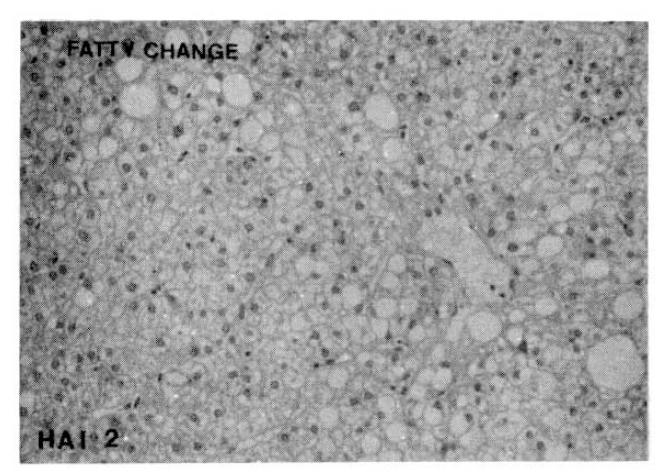

7. Fatty Change

Fatty change could not be detected in 57.9% of the CAH-C group and 68.4% of the CAH-B group, respectively. There was no significant difference in the morphologic feature of fatty cange between these two groups (Table 11, Fig. 8).

Fatty Change

Fig. 8.

Histopathologic appearance of fatty change, moderate grade (HAI 2).